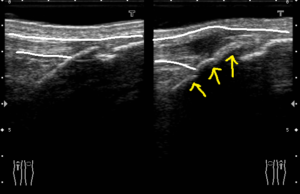

膝の疾患では「オスグッド病」になる方が多くあります。この疾患は急な成長が起きた時に、練習や試合のスケジュールが過密になると誰にでも起きます。本人でも確認できるので運動時の痛みがない段階でも圧迫して痛みがある場合では、練習を控えたり太ももの前面のストレッチやマッサージを継続することで症状の深刻になることを防げます。成長が止まる時期には症状が落ち着くことが多いのですが、はがれた軟骨部が骨化して炎症が続く場合は手術にて骨片を取り除くこともあります。

当院ではエコーにて上記の図のような画面で鑑別します。現在の状況を説明し治療を行いますので安心してください。並行して運動療法などの指導・サポーター使用時の注意事項等の説明も行います。